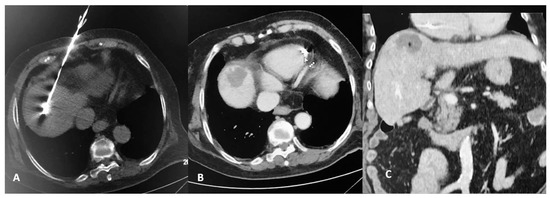

2.2. Percutaneous MW Ablation Procedure